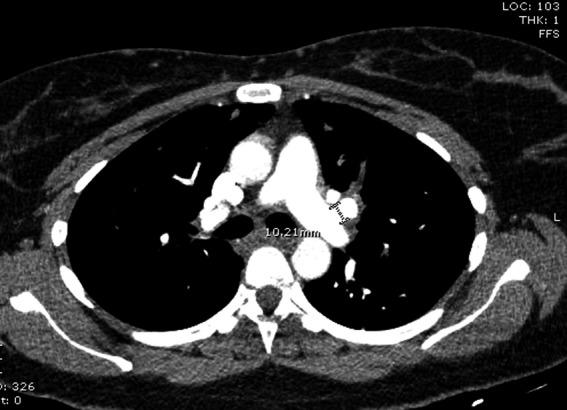

Pulmonary artery pseudoaneurysm is an uncommon yet fatal clinical entity. Its presentation can mimic a number of common diseases and can be easily missed. As pseudoaneurysm is associated with a number of fatal complications, clinicians should be aware of imaging features which distinguishes pseudoaneurysms from its close differentials. Early recognition and treatment of pseudoaneurysm can prevent fatal outcomes including hemothorax, rupture, or death.